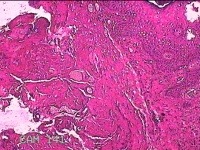

右耳前瘘管

性别

男

年龄

53岁

临床诊断

一般病史

反复右耳前红肿、流脓2月。

标本名称

大体所见

灰白暗红色组织.3x0.8x0.3cm一块,表面糜烂,切面灰白暗红色,质中。